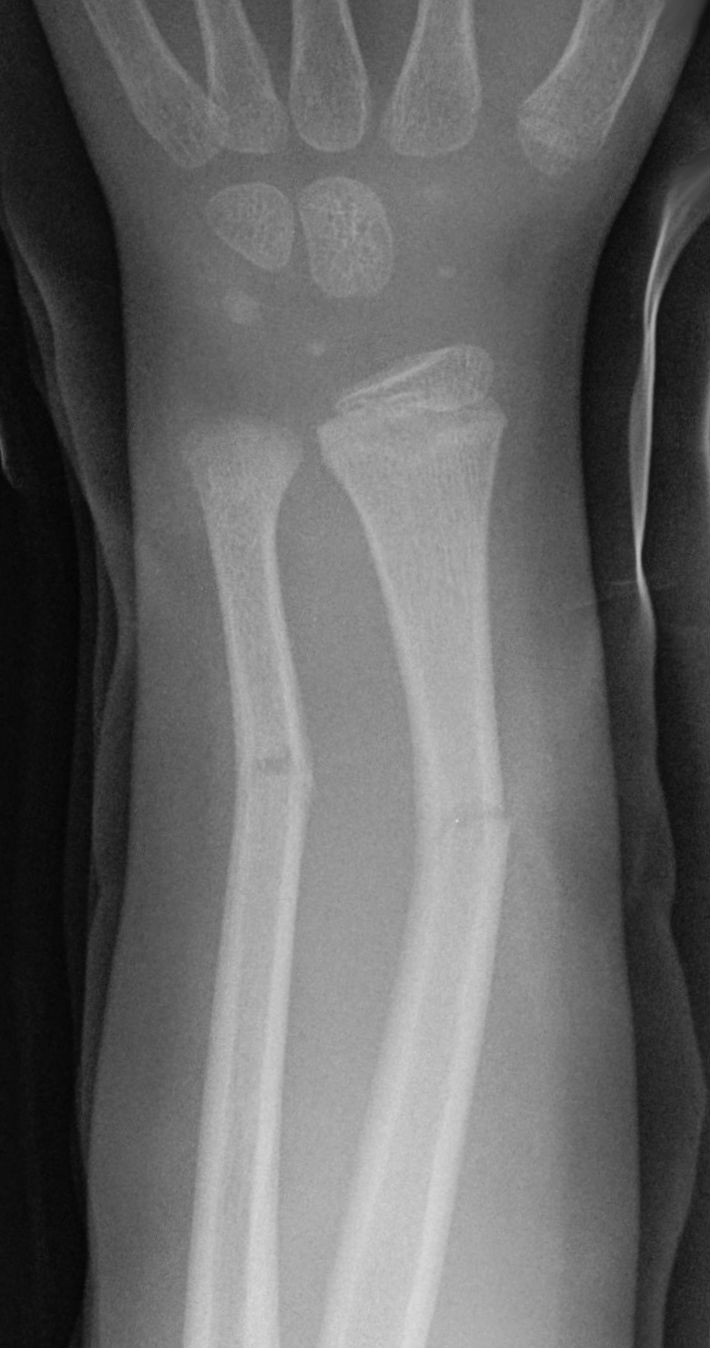

Q.7. What's the xray finding?

Correct Answer : B